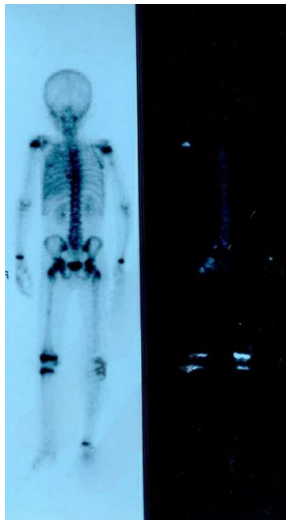

Bone scanning: hypodense foci on the left and right thight, from which biopsies were taken and the bone tissue were normal, with no malignancy.

Bone scintigraphy: foci of enhacement of the material (radioactive Technetium) in the distal third of the thight, with increased fixation of the radioactive material in the posterior end of the eight vertebra, no metasis.